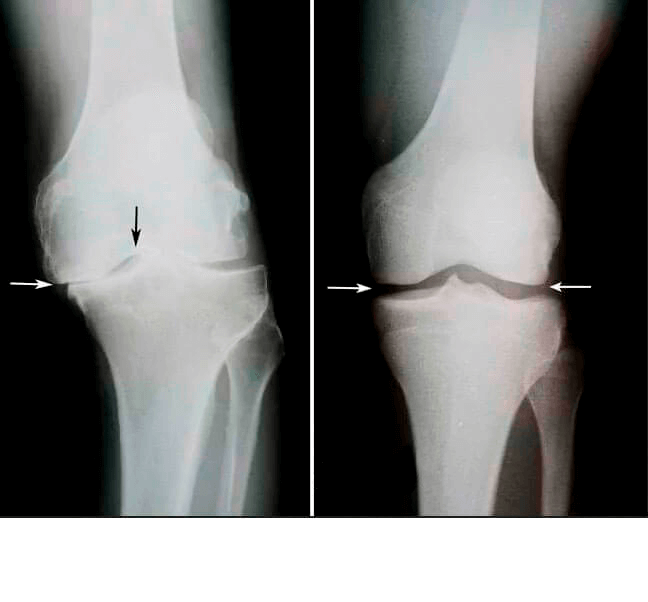

Tavsiye için bana döndü, 1.5 ay sürdüğü söylenen Chondrostart ve servikal omurganın ikinci bir röntgeni için reçete edilen röntgene baktım.